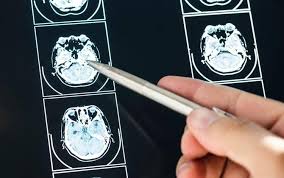

La ricerca, guidata da scienziati della NYU Langone Health e finanziata dal National Institutes of Health, è stata pubblicata sulla rivista Alzheimer’s & Dementia e si concentra su alterazioni strutturali e molecolari osservate nel cervello di pazienti con Long Covid rispetto a controlli senza sintomi persistenti.

Un elemento chiave dello studio riguarda il plesso coroideo (CP), una rete di vasi sanguigni nel cervello che produce il liquido cerebrospinale e funge da importante barriera immunitaria e filtro di rifiuti metabolici. Nei pazienti con Long Covid è stato osservato che il CP è in media circa il 10% più grande rispetto a chi ha avuto il Covid senza sviluppare sintomi a lungo termine.

L’aumento del volume del plesso coroideo è associato a livelli più elevati di biomarcatori legati a malattie neurodegenerative, come la proteina pTau217 e la proteina acida fibrillare gliale (GFAP), entrambe note per essere implicate nei processi patologici dell’Alzheimer.

Le alterazioni strutturali osservate si accompagnano anche a ridotti flussi sanguigni nel tessuto cerebrale e a una performance cognitiva leggermente inferiore nei test come il Mini-Mental State Examination, con un decremento medio di circa il 2%.